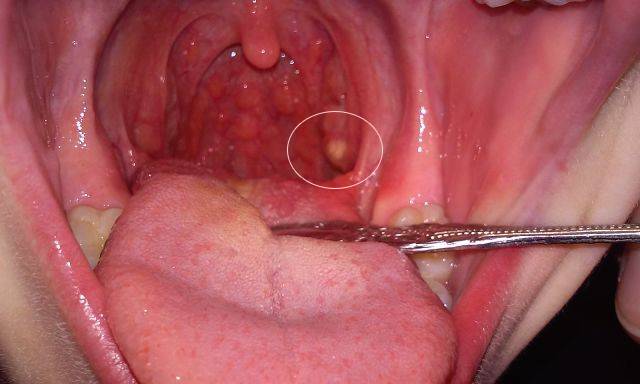

Гной на миндалинах имеет характерный вид: округлые, слегка выступающие наружу белесоватые пятна. Частые спутники хронического тонзиллита представляют собой заполненные гноем лакуны. Увидев фото гнойной пробки, распознать такую картину в собственном горле не сложно. Остальные отделы горла выглядят здоровыми, иногда появляется покраснение небных дужек. Глубоко расположенные пробки приводят к зарастанию лакуны, гной распространяется на клетчатку, могут образовываться абсцессы.

Гной в горле имеет специфический вид: пятна округлой формы, слегка выступающие наружу.

Хронический тонзиллит часто сопровождается появлением заполненных гнойной жидкостью лакун. Поражение распространяется только на миндалины, остальные отделы горла при этом выглядят здоровыми, лишь иногда отмечается покраснение нёбных дужек. Пробки, расположенные глубоко, способны привести к зарастанию лакуны, гнойная жидкость распространяется на клетчатку, возможно образование абсцессов.